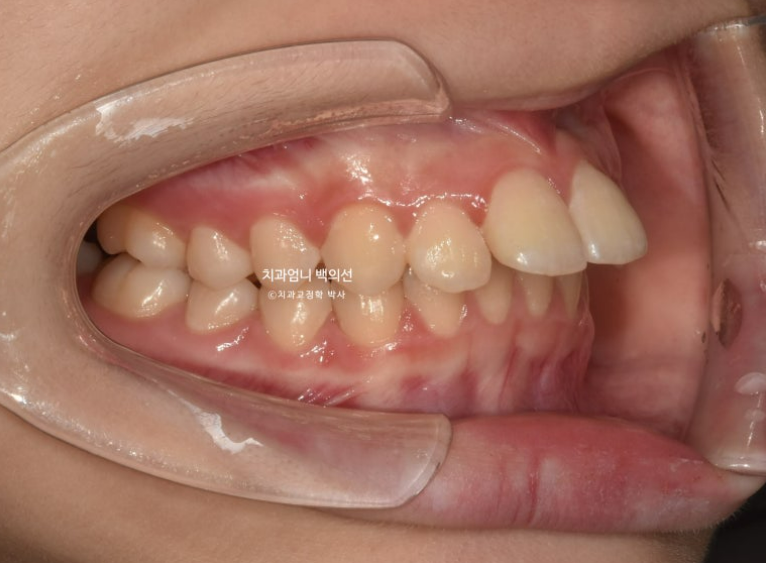

치료시작 9개월째 모습입니다.

파란 화살표의 브라켓 주변 희끗한 부분은 양치가 잘 안되어 탈회된 부분입니다.

치아가 삭았다라고도 하고 정체는 초기충치입니다.

클리피씨 교정은 인비절라인과 다르게 양치질 할 때 장치 및 설차 주변을 깨끗하게 닦기가 힘듭니다.

충치가 많고 양치질이 잘 안되는 분들에게는 같은 진단이라면 클리피씨보다 인비절라인을 더 권유하는 이유입니다.

이런 초기충치가 보이는 환자분들께는 불소도포를 주기적으로 해주고 양치질 교육에 힘쓰고 있습니다.